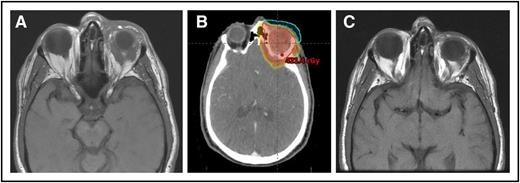

(A) A 64-year-old man with MZL of the left orbit. (B) An intensity-modulated RT plan of 24 Gy was designed, but only 4 Gy was delivered with near-CR obtained. (C) Seven months’ follow-up after only 4 Gy with no progression.

Advances in tumor imaging and radiation treatment planning, targeting, and delivery as well as a larger menu of RT systems (including intensity-modulated RT, electrons, and protons) provide an opportunity for more conformal treatment and a possibility of safely reducing the irradiated volume in the orbit in selected cases, particularly when the MZL is limited to the conjunctiva or lacrimal gland. Yet, the standard recommendation for most cases is to still include the full orbital contents unless the disease is confined to the conjunctiva (see figure).

More recently, a very low dose of only 4 Gy (2 Gy ×2) was shown to be adequately effective in a prospective randomized study from the United Kingdom, and a group from Stanford reported on their favorable experience with this low-dose schedule.8,9